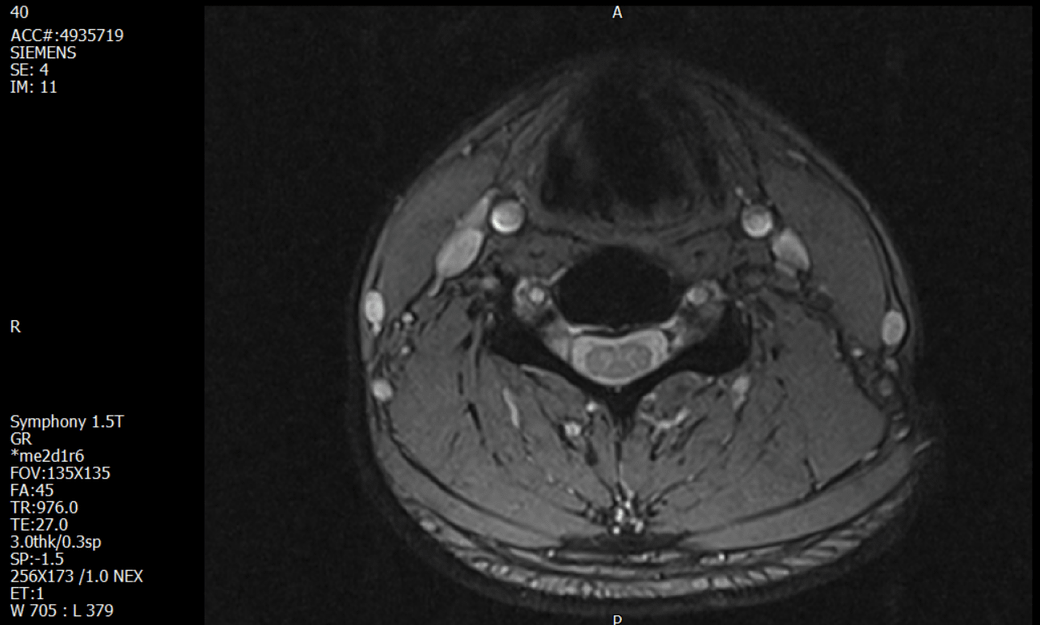

경추 요추 디스크 MRI판독 부탁드립니다.

- 3개월전 좌측 상지 저림(힘빠짐) 발생. 이틀뒤 에 좌측 하지 저림(힘빠짐) 발생.

(힘이 축처지는 느낌이라서 힘빠짐이라고 하지만, 실제 근력 문제, 감각이상, 활동 문제 없음)

-11월, 증상발생 직후 잠실소재 척추전문병원 MRI 요추경추 촬영 후 신경외과 박사 진료, 허리는 매우 건강, 경추는 퇴행성 진행되고 있지만 디스크라고 보기 어려움. 신경막만 살짝 건드리는 정도고 이 정도로 힘빠짐이나 저림이 오지 않고 원인은 다른 곳에 있을 가능성.

-12월, 분당서울대병원 재활의학과 진료, MRI 영상보고 딱히 다른 말은 없었음. 근전도 검사해보자 해서 신경전도, 근전도 검사 진행, 검사결과 이상없었고, 신경쪽 문제는 아예 배제해도 될것이라고 함. 정신쪽에 기인한 문제일 가능성 제시.

-올해 1월, 국립암센터 재활의학과 진료, 병명을 찾기가 쉽지 않을 것

-올해 1월, 분당서울대병원 신경과 진료, MRI영상보더니 디스크가 있고 저림과 힘빠짐이 이에 기인했을 가능성이 충분히 있다고함. (경추만 말한것인지 요추도 포함인지 모르겠으나 디스크 시술 방안을 제시함) , 팔다리가 우연이 동시에 저림이 올수 있는지에 대해서 물었더니 이틀 상간으로 발생했기 때문에 동시라고 보기 어렵다고함...

1. MRI 상 , 경추와 요추에 디스크가 있나요? 있다면 좌측 팔과 다리에 저림 및 힘빠짐을 줄 정도인가요?

• 1. MRI 사진을 보았을 때 디스크를 의심해볼 수 있는 소견이 살짝살짝 보이긴 합니다만, 상하지의 저림 및 힘빠짐을 유발할 정도인지는 솔직히 회의적입니다.

2. 영상의 퀄리티는 나쁘지 않아 보입니다. 굳이 재촬영을 하실 필요는 없어 보입니다.

3. 개인적으로는 디스크로 인한 증상이 아닐 것으로 보나, 만약 디스크가 맞다면 우연하게 목과 허리 디스크 발병이 이틀 간격을 두고 나타났을 가능성을 생각해야 하는데, 현실적으로 그 가능성이 높지 않습니다.

4. 말씀하신 것처럼 특히 요추부 MRI는 디스크를 찾기 어렵습니다.

상기 MRI 소견으로는 심한 증상을 보일 정도는 아니며 디스크의 가능성은 적어보입니다.